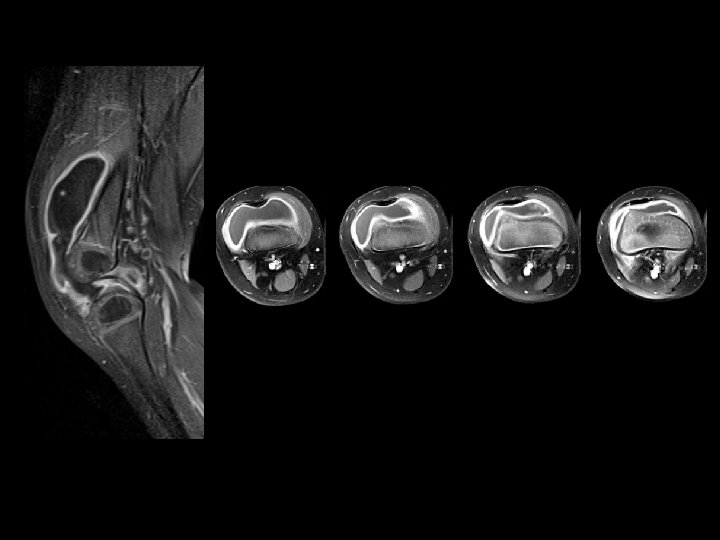

Ménisques • Attention au signal méniscal : plus élevé que chez l’adulte, ressemble à des ménisques dégénératifs d’adultes ! • Avant 12 ans, une image linéaire centrale horizontale est un vaisseau nourricier.

Ménisques • Une lésion méniscale peut révéler un ménisque discoïde • Blocage, pseudo blocage

Gros ménisque en hypersignal